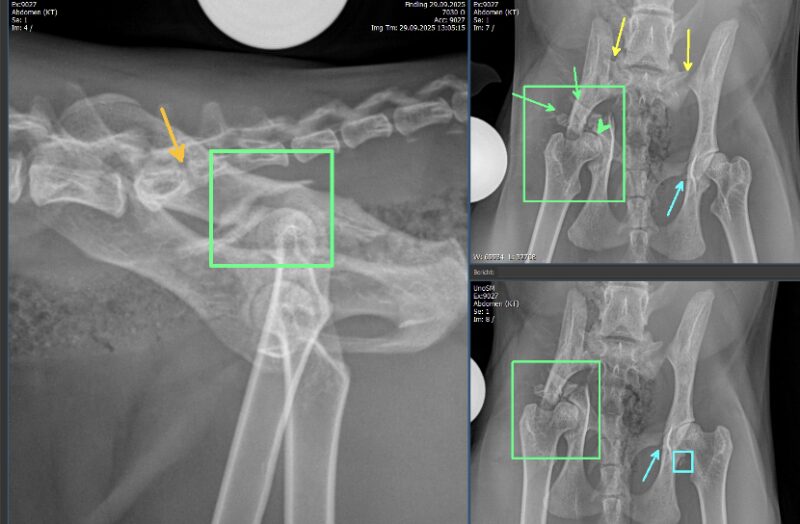

Besten Dank für die Übermittlung dieses spannenden Falles! Es liegen Röntgenbilder des Thorax und des Abdomens in 2 Ebenen vor (sinistro-dextraler Strahlengang, sowie ventro-dorsaler Strahlengang). Wesentliche Hauptbefunde sind im Bereich des muskuloskelettalen Systems, als auch im Abdomen zu vermerken.

Mehrfrageant-Fraktur am rechten Acetabulum. Zum einen besteht am rechten Acetabulum eine Mehrfrageant-Fraktur mit sicherer Beteiligung des Iliums (grüne Rechtecke). Die rechte Darmbeinschaufel ist nach mediokaudal rotiert, wodurch der Beckenkanal kranial des Acetabulums erweitert erscheint. Zusätzlich besteht eine kaudale, sowie minimal dorsale Verschiebung der Darmbeinschaufel, wodurch in der ventro-dorsalen Aufnahme der Trochanter major überlagert wird. Kranio-lateral des rechten Aceatbulums sind mindestens zwei längliche, teils scharfrandige, teils geringgradig irreguläre Knochenfragmente erkennbar (grüne Pfeile). Das Acetabulum selbst ist, soweit beurteilbar, artikuliert mit dem Femurkopf. Eine Beteiligung des rechten Os pubis kann aufgrund der Überlagerung nicht ausgeschlossen werden. Der Gelenkspalt ist jedoch gering- bis mittelgradig erweitert (grüner Pfeilkopf).

Iliosakrale Gelenksluxation: Linksseitig besteht zudem eine iliosakrale Gelenksluxation, wodurch das Becken nach kranioventral verschoben ist und eine geringgradige linksseitige latero-kaudale Rotation entsteht (gelbe Pfeile). Das rechte Iliosakralgelenk ist fraglich subluxiert.

Transversale Fraktur: Eine transversale, minimal irreguläre, vollständige Fraktur ist am lateralen Aspekt des linken Os pubis erkennbar (blaue Pfeile). Diese resultiert in keiner nennenswerten Knochendeviation. Am kaudolateralen Rand des linken Acetabulums befinden sich multiple kleine Fragmente (blaues Rechteck). Im umliegenden Weichteilgewebe ist weder freies Gas erkennbar, noch besteht eine deutliche Weichteilschwellung.

Verwachsene Wirbelkörper: Der S1 Wirbelkörper ist unvollständig mit dem Wirbelkörper des S2 verwachsen (orangener Pfeil). Bilateral besteht jedoch eine Artikulationsfläche beider Ala ossis sacri.